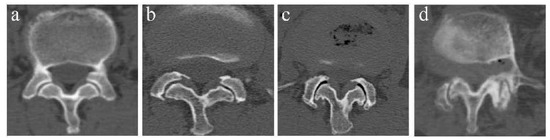

2.4.1. Lumbar Lordosis Angle, L4 Inclination Angle, and Pelvis-Related Parameters

Lumbar lordosis (LL): The sagittal angle between the L1 upper endplate and the tangent of the S1 upper endplate. L4 inclination angle (L4IA): The intersection between the tangent line and the horizontal line at the lower margin of the fourth lumbar vertebra. Pelvic incidence (PI): The angle between the perpendicular to the upper sacral endplate at its midpoint and the line connecting this point to the femoral head axis. This is a morphological parameter that is considered to be a constant and has nothing to do with the spatial orientation of the pelvis. Sacral slope (SS): The angle between the horizontal and the upper sacral endplate. It is a positional parameter, which varies according to the pelvis position. Pelvic tilt (PT): The angle between the vertical and the line passing through the midpoint of the sacral plate to the axis of the femoral head. It is also a position parameter (Figure 1).

Figure 1.

This illustration displays the pelvic incidence (PI), the sacral slope (SS), the pelvic tilt (PT), the lumbar lordosis (LL), and the L4 inclination angle (L4IA).